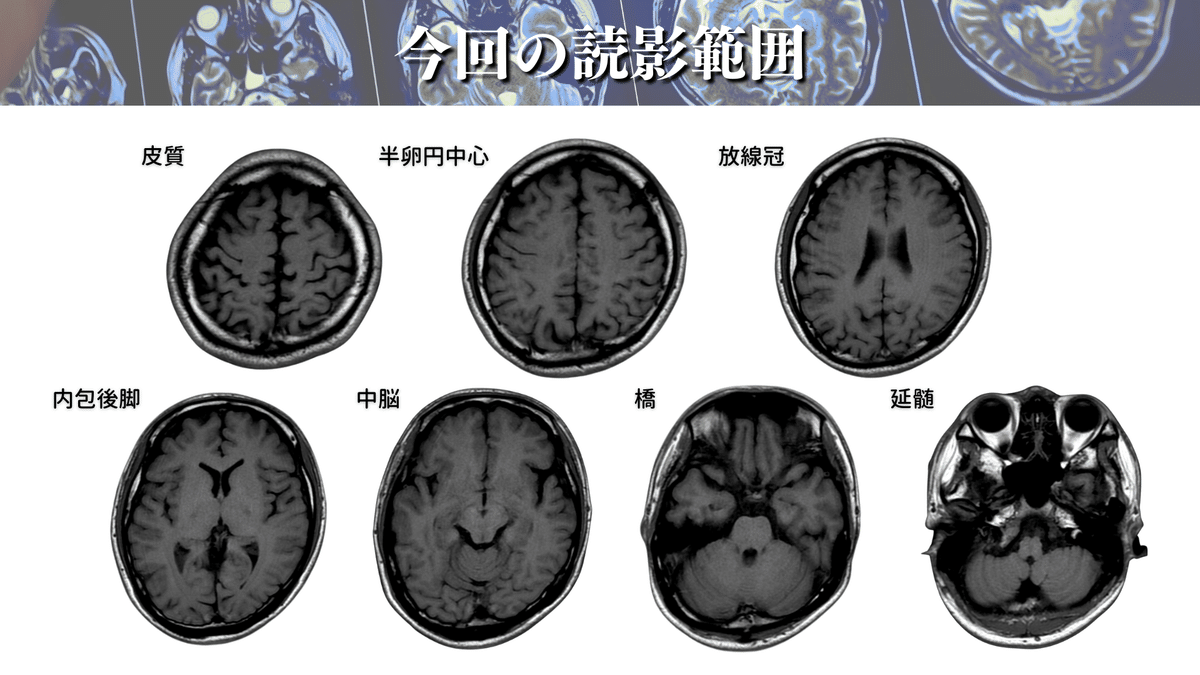

今回読影する範囲はコレ!

では、早速読影していきましょう!

読影していくのは以下の範囲になります🧠

さらに詳しく見ていくと、下図のようなポイントを通過していきます🏃♀️

CSTの代表的な通過ポイント

・一次運動野(6野や3.1.2野からの出力もあります)

・半卵円中心

・放線冠

・内包後脚

・大脳脚(中脳)

・橋

・延髄(錐体交叉)

MRIで見るとこんな感じです⬇️

かなりイメージできてきたのではないでしょうか🤭?